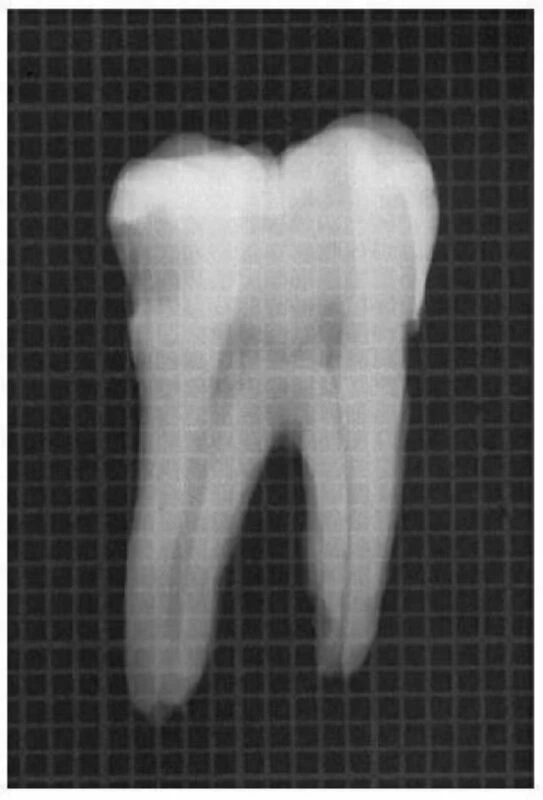

Hình 11.14. A. Phim trước điều trị R36: chân gần cong 1/3 trên. B. Mở đầu bằng trâm số #8 đi vào ống ngoài gần, nhận thấy ống tủy cong về phía xa và phía lưỡi. C. Xoang tủy được mở rộng về phía gần và phía má, phạm vào múi gần ngoài. D. Trâm số #20 có một đường vào thẳng đến 1/3 chóp của ống tủy.